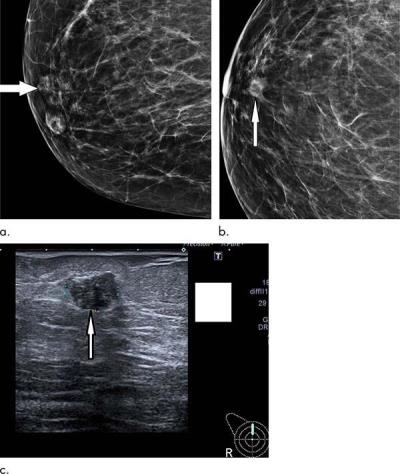

Figure 2: Routine screening mammogram in a 67-year-old woman shows subtle 12-mm asymmetric density with ill-defined margins representing small grade 3 cancer (arrow) on (a) lateral oblique view and (b) cranio-caudal view; it is difficult to see even on digital mammogram in a nondense breast. Subsequent clinical examination was normal. (c) US confirmed 12-mm irregular hypoechoic mass (arrow). Patient underwent wire-guided surgical excision and sentinel node biopsy. Final histologic examination showed 14-mm grade 3 invasive ductal carcinoma, which was node negative.